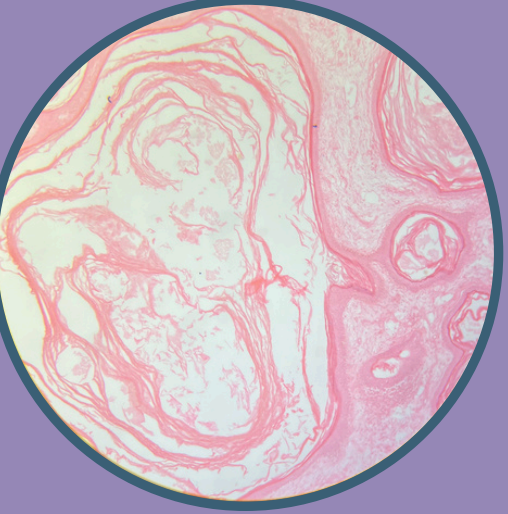

Fibroadenoma

Neoplasia benigna bifásica con afectación de ductos y estroma

Colapso de ductos por sobreproducción de estroma

Estroma compuesto principalmente por tejido fibroso que rodea y sostiene las estructurales glandulares

Fibroadenoma:

Estroma compuesto principalmente por tejido fibroso que rodea y sostiene las estructuras glandulares